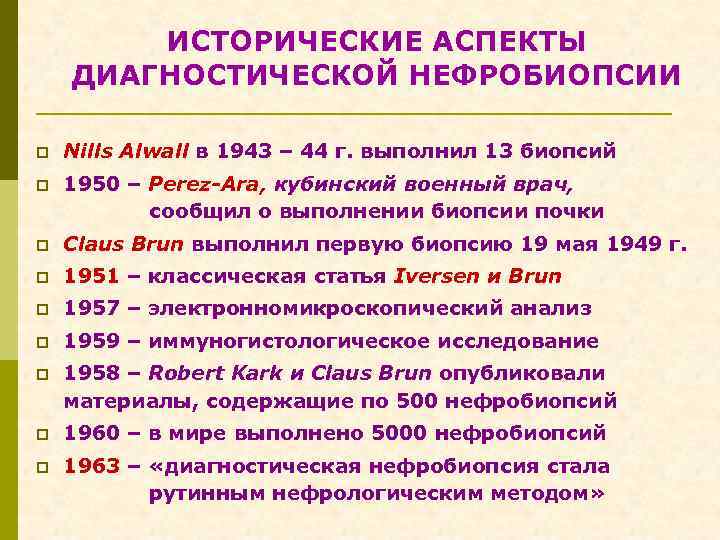

ИСТОРИЧЕСКИЕ АСПЕКТЫ ДИАГНОСТИЧЕСКОЙ НЕФРОБИОПСИИ p Nills Alwall в 1943 – 44 г. выполнил 13 биопсий p 1950 – Perez-Ara, кубинский военный врач, сообщил о выполнении биопсии почки p Claus Brun выполнил первую биопсию 19 мая 1949 г. p 1951 – классическая статья Iversen и Brun p 1957 – электронномикроскопический анализ p 1959 – иммуногистологическое исследование p 1958 – Robert Kark и Сlaus Brun опубликовали материалы, содержащие по 500 нефробиопсий p 1960 – в мире выполнено 5000 нефробиопсий p 1963 – «диагностическая нефробиопсия стала рутинным нефрологическим методом»

ИСТОРИЧЕСКИЕ АСПЕКТЫ ДИАГНОСТИЧЕСКОЙ НЕФРОБИОПСИИ p Nills Alwall в 1943 – 44 г. выполнил 13 биопсий p 1950 – Perez-Ara, кубинский военный врач, сообщил о выполнении биопсии почки p Claus Brun выполнил первую биопсию 19 мая 1949 г. p 1951 – классическая статья Iversen и Brun p 1957 – электронномикроскопический анализ p 1959 – иммуногистологическое исследование p 1958 – Robert Kark и Сlaus Brun опубликовали материалы, содержащие по 500 нефробиопсий p 1960 – в мире выполнено 5000 нефробиопсий p 1963 – «диагностическая нефробиопсия стала рутинным нефрологическим методом»